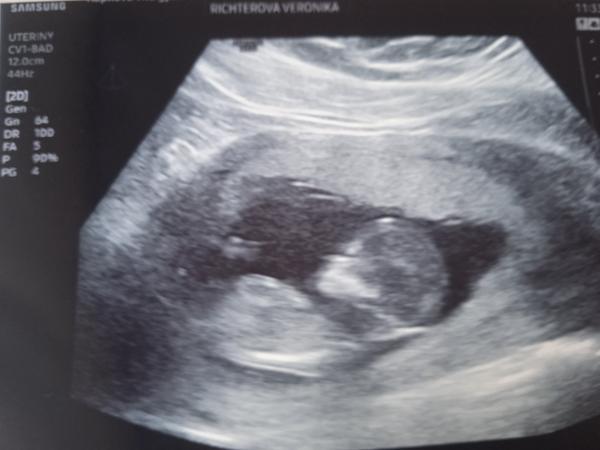

@anickaaa28 ahojky Aničko, tak v úterý proběhl screening. Krev negativní a ultrazvuk celý v pořádku❤️🍀malé se vyvíjí dobře. Má vše, co má mít. Už má přes 6cm bobisek .Máš krásnou fotečku, já z toho pláče a nervozity jsem si o foto neřekla až sestřička se mě zeptala zdali mám fotku řekla že ne a ona letěla za Dr. A donesla mi obyč černobílou. Já to nevydržela a dnes jela znova aby mi udělal 3D no male se rozhodlo že bude stávkovat. Nešlo ho zachytit vyfotil mi i tak na mě přání ,ale nic na tom není jen obrys a ještě rozmazany., dobře navíc jsem silnější tak mi řekl že mám přijít za měsíc ale už to nechám na ten 20tt. Posílám foto alespoň to které mám. Tak se zatím opatruj a dáme si opět vědět.🍀🍀🍀